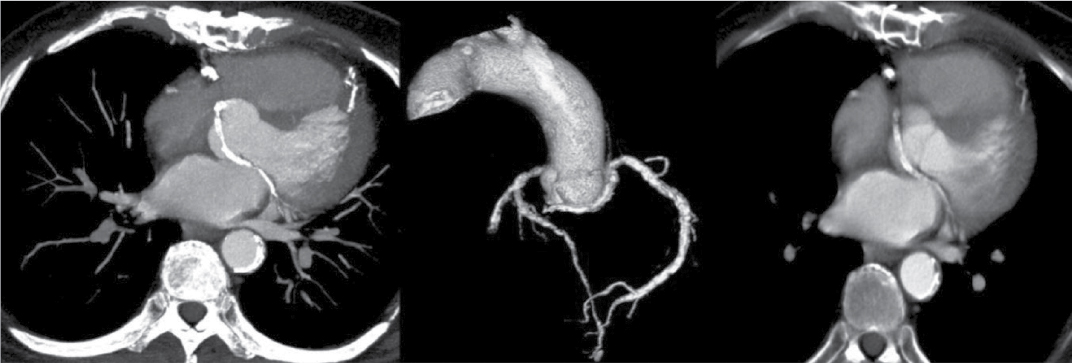

Figure 2. VRT and axial images of a patient (55/F) showing RCA originating from left coronary sinus of Valsalva. Course of RCA is interarterial.

Figure 3. VRT and axial images of a patient aged 59/M depicting the origin of LCA from RCA having interarterial course.

At Nizam’s Institute of Medical Sciences (NIMS), Hyderabad, 770 patients underwent CT-conventional coronary angiography (CAG), on 128-slice single source MDCT (SOMATOM Definition AS ± SEIMENS) during the last 3 years (unpublished data). On analysis, coronary artery anomalies were found in 23 patients (3%). Their ages ranged from 25 to 82 years. Majority of the cases were in 51 to 60 years age group. Among them, 17 were males. The most common anomaly seen was high take-off of coronary arteries, seen in 10 cases. Of them, 2 were having high origin of right coronary artery (RCA) (Fig. 1), 7 were having high origin of left main coronary artery (LMCA) and one was having high origin of both coronary arteries with acute kink at the origin of RCA. Anomalous origin of coronary artery from opposite sinus was seen in 8 cases (Figs. 2-5). RCA from left coronary sinus with interarterial course between aorta and right ventricular outflow tract was seen in 5 cases. Anomalous origin of left coronary artery (LCA) from right coronary sinus with interarterial course between aorta and right ventricular outflow tract was seen in 2 cases. Anomalous origin of left circumflex artery (LCx) from right coronary sinus with retroaortic course was seen in 1 case (Fig. 6). Separate ostia for left anterior descending artery (LAD) and LCx was noted in 3 patients (Figs. 7 and 8). Shepherd crook deformity of proximal segment of RCA was seen in 1 patient. Super-dominant RCA with absent LCx was seen in 1 patient (Fig. 9).

Origin of coronary artery or branch from the opposite or noncoronary sinus is another anomaly that is commonly observed. These anomalies are classified into 4 types. One is interarterial course between aorta and pulmonary artery. Second one is retroaortic course. Third is prepulmonic and septal or subpulmonic course. The interarterial course is clinically important as it is associated with sudden death.5 Fujimoto et al, in their series of 5,869 cases, noted that 29 cases had opposite coronary sinus and in 27 of these cases RCA arose from left coronary sinus.4 All these cases had interarterial course. It is reported that 30% of these have sudden cardiac death. Anomalous origin of coronary artery from opposite sinus was seen in 8 cases accounting for 1.04%. RCA from left sinus were 5 and LCA from right coronary sinus were 2 with interarterial course. In 1 case, LCx was arising from right coronary sinus with retroaortic course.